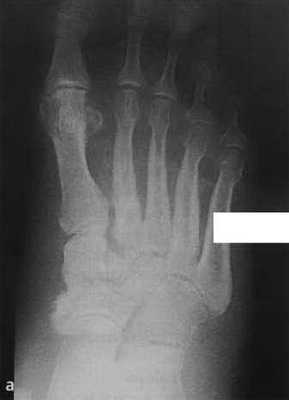

а,b Нейропатическая остеоартропатия стопы у мужчины 69 лет с длительным течением сахарного диабета:

а) Рентгенологическое исследование стопы демонстрирует места деструкции кости в основании второй плюсневой кости. Остеосклеротические изменения поражают ладьевидную кость по направлению к медиальной клиновидной, а также промежуточную клиновидную по направлению ко второй плюсневой кости.

b) Т1 -взвешенная МРТ после введения контрастного вещества демонстрирует отек мягких тканей и отечные предплюсневые кости, так же как кистозные изменения и явления синовита.